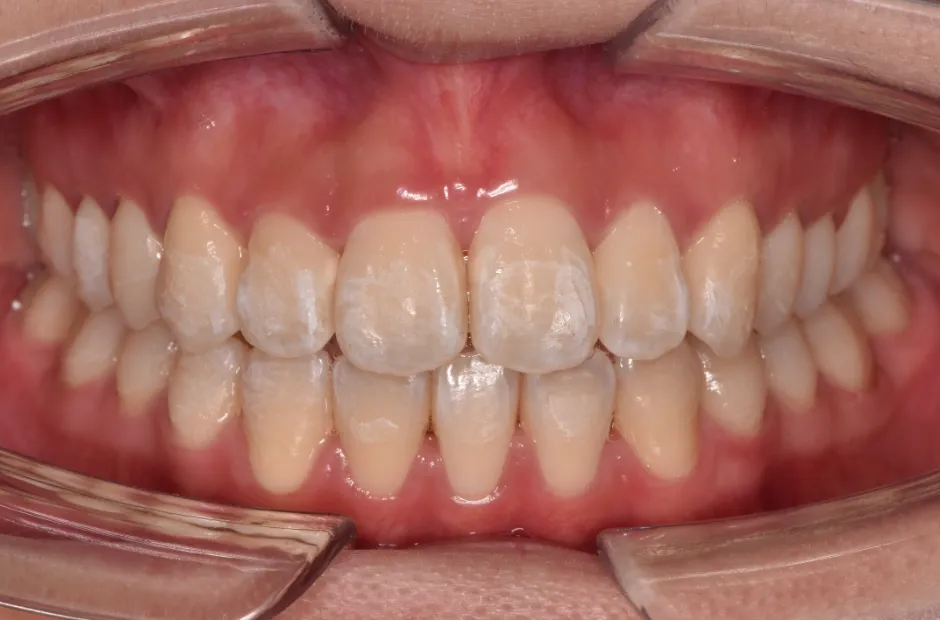

治療症例

ブラケット矯正

前歯部反対咬合

| 診断名・主訴 | 前歯部反対咬合 |

|---|---|

| 年齢・性別 | 14歳・男性 |

| 治療期間・回数 | 1年2か月 |

| 治療に用いた主な装置 | ブラケット矯正 |

| 抜歯部位 | なし |

| 治療費 | 60万円(税抜) |

| リスク・副作用 | 装置による違和感・疼痛・歯肉退縮・歯根吸収・虫歯のリスクなど |

治療後